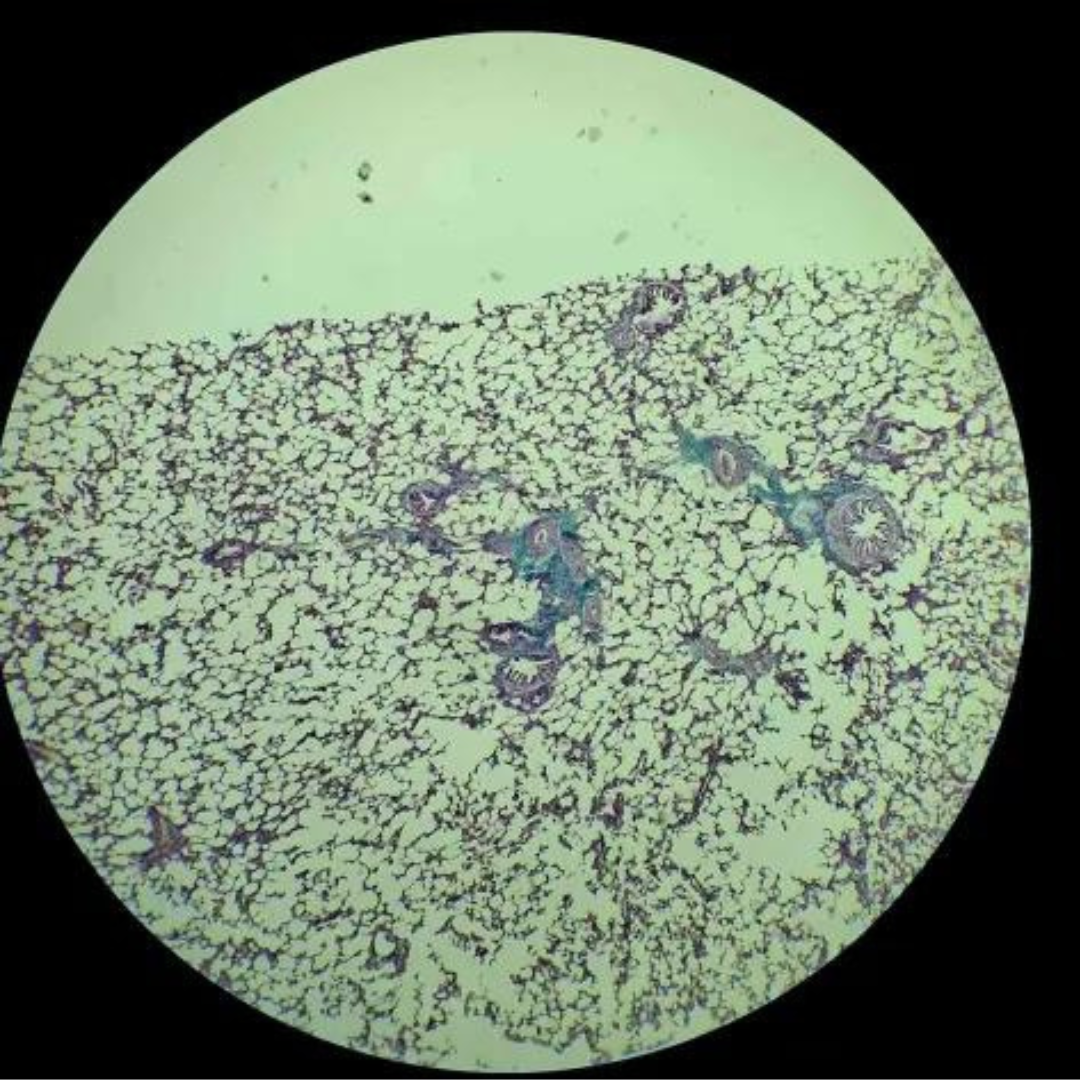

Lungs

Lungs

Lungs

Lungs

Lungs

Lungs

Lungs